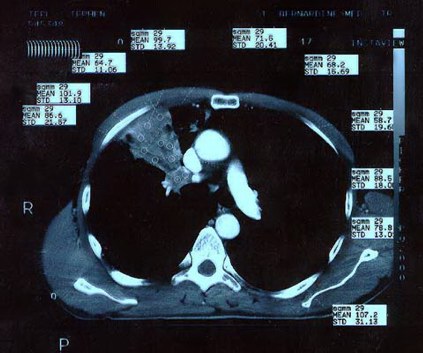

Scan 15th March 1999 No2